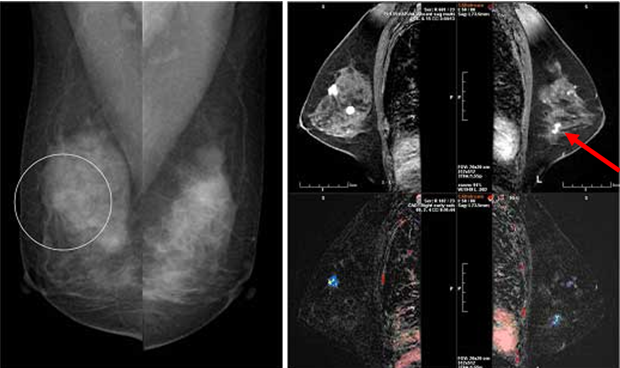

유방에 있는 2cm 길이의 덩어리를 결절이라고 하고 이 크기보다 큰 것을 덩어리라고 합니다. 덩어리는 가장 흔한 증상으로 유방암 증상의 약 70%를 차지합니다. 흔히 유방 덩어리를 만질 때 통증이 없다고 생각하는데 이는 잘못된 것입니다. 대부분의 덩어리는 통증이 없으므로 젊은 여성이 자가 검진을 통해 덩어리를 느끼면 암이라고 생각하고 병원에 가는 것이 좋습니다. 20대의 경우 유방암 발병률은 2.2%입니다.